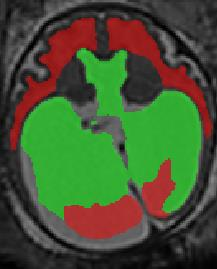

Limiting failures of machine learning systems is of paramount importance for safety-critical applications. In order to improve the robustness of machine learning systems, Distributionally Robust Optimization (DRO) has been proposed as a generalization of Empirical Risk Minimization (ERM). However, its use in deep learning has been severely restricted due to the relative inefficiency of the optimizers available for DRO in comparison to the wide-spread variants of Stochastic Gradient Descent (SGD) optimizers for ERM. We propose SGD with hardness weighted sampling, a principled and efficient optimization method for DRO in machine learning that is particularly suited in the context of deep learning. Similar to a hard example mining strategy in practice, the proposed algorithm is straightforward to implement and computationally as efficient as SGD-based optimizers used for deep learning, requiring minimal overhead computation. In contrast to typical ad hoc hard mining approaches, we prove the convergence of our DRO algorithm for over-parameterized deep learning networks with ReLU activation and a finite number of layers and parameters. Our experiments on fetal brain 3D MRI segmentation and brain tumor segmentation in MRI demonstrate the feasibility and the usefulness of our approach. Using our hardness weighted sampling for training a state-of-the-art deep learning pipeline leads to improved robustness to anatomical variabilities in automatic fetal brain 3D MRI segmentation using deep learning and to improved robustness to the image protocol variations in brain tumor segmentation. Our code is available at https://github.com/LucasFidon/HardnessWeightedSampler.